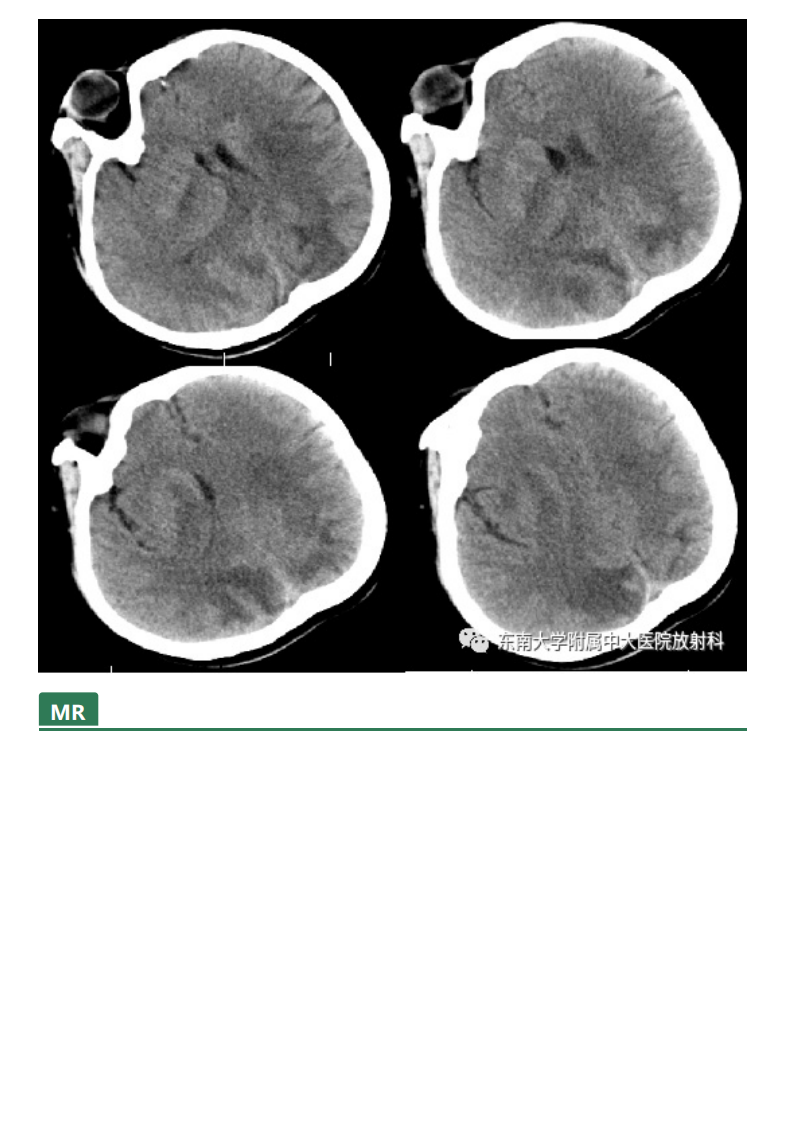

20210415_2【晨读结果公布】2021.04.14神经系统疾病——可逆性后部脑病综合征(PRES).pdf